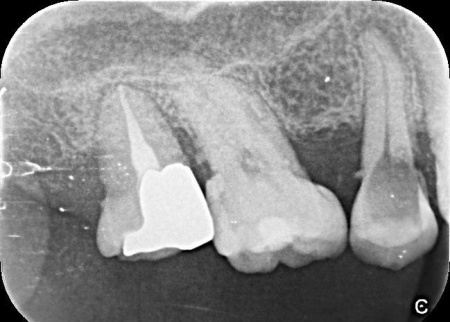

| 診断 | 拝見したところ、右上の歯に深い虫歯が見つかりました。

レントゲン撮影で詳しく検査した結果、虫歯が神経まで進行しており、歯根の先に黒い影が確認できます。 このまま放置すると、炎症が広がって歯を支える骨が溶けるおそれがあるため、早急に治療をする必要があると診断しました。 |

治療前